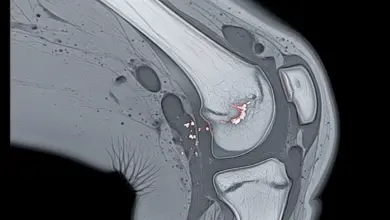

A artrose do joelho é um processo de desgaste articular. A cartilagem perde qualidade, a articulação passa a absorver pior a carga e o movimento deixa de acontecer com a mesma eficiência.

Em muitos casos, também existe inflamação local, rigidez e alteração mecânica do joelho.